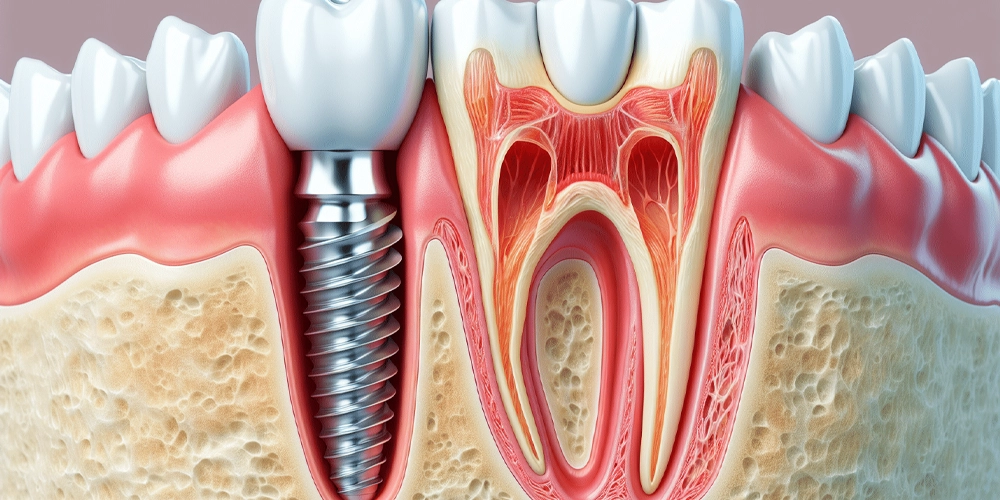

Les implants dentaires sont des vis en titane qui servent de racines artificielles. Placés chirurgicalement dans l’os de la mâchoire, ils fusionnent avec l’os pour fournir une base solide aux prothèses dentaires comme les couronnes, les ponts ou les dentiers. Cette solution permanente restaure efficacement la fonction et l’esthétique des dents manquantes, améliorant la mastication, la parole et la confiance globale d’une personne.

- Procédure : Pose d’implant dentaire.

- Durée : Dure généralement de 30 minutes à 2 heures.

- Anesthésie : Une anesthésie locale est utilisée pour votre confort.

- Récupération : L’implant a besoin de 3 à 6 mois pour fusionner avec l’os. Une prothèse temporaire peut être utilisée pendant cette période.